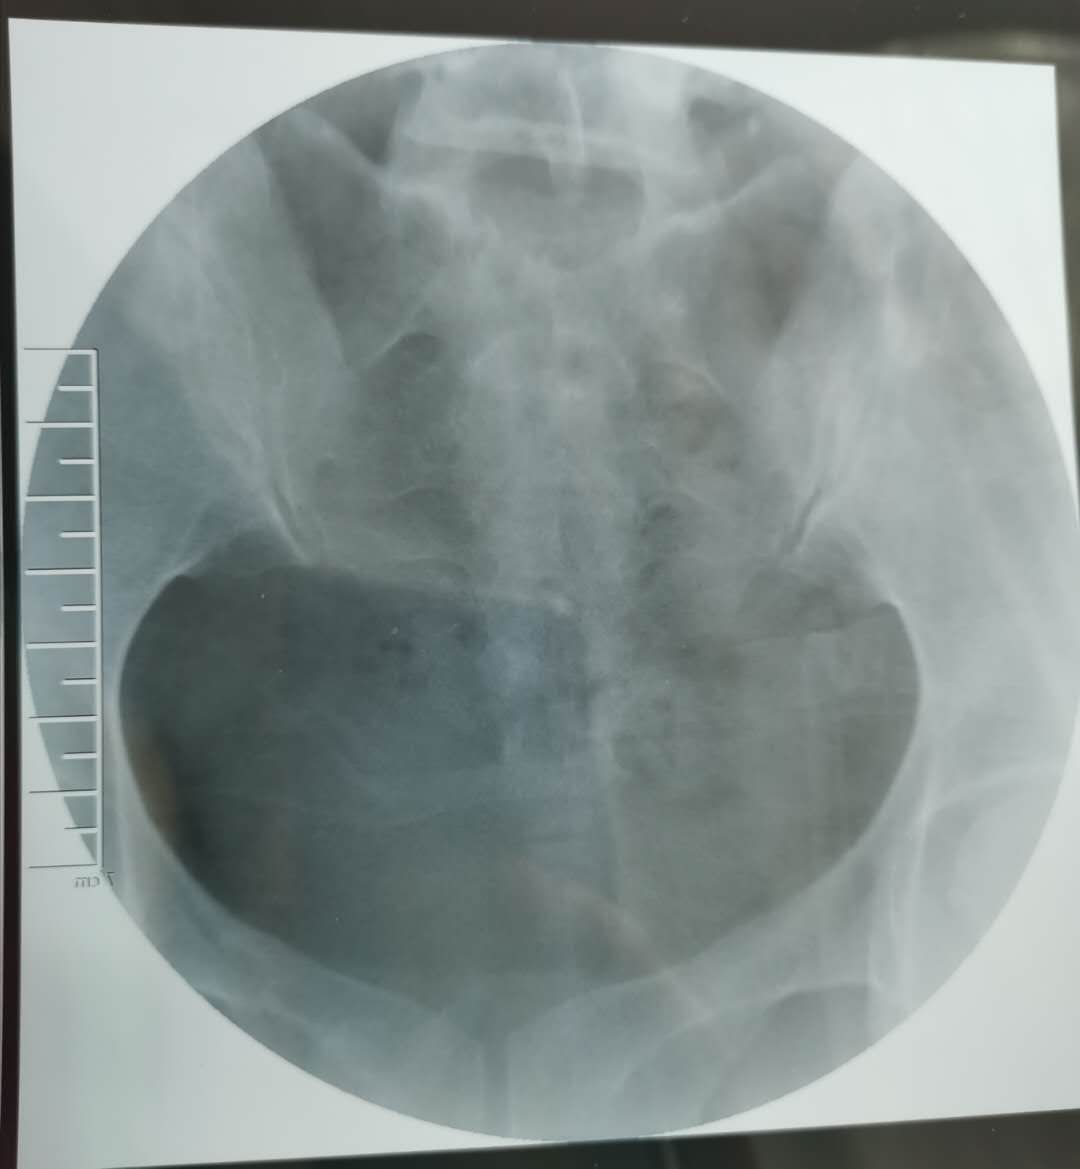

我这个是做了输卵管介入手术,请问输卵管是通了

做完输卵管造影第六天了小腹还是感觉沉甸甸的如

可以热敷腹部,如果有发热,腹痛加剧,白带量多,有异味,随时就医